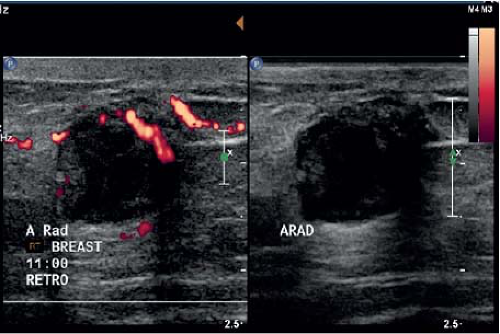

If the appearance is classic “flame shaped” on mammogram and there is NO evidence of a mass, then US should be avoided as this will usually lead to an unnecessary biopsy. US is indicated if the mammogram demonstrates a visible mass or the palpable breast mass is located away from the nipple (Fig. 19-3). Figure 19-4 demonstrates a left subareolar mass with convex borders and coarse calcifications on mammography. Calcifications seen on mammography deserve workup in the male breast. Magnification views should be performed to determine extent and

In the male breast, the majority of malignancies are subareolar and metastasis to the axilla is common. It has been reported that 50% of men have axillary nodal metastasis at initial presentation (9). US of the ipsilateral axilla should be included. It is important to note the morphology of the nodes matters more than the overall size. Displacement of the fatty hilum, increased cortical thickness >3 mm or irregular contour of the cortex are suspicious findings and warrant tissue sampling (Fig. 19-5). If US-guided axillary lymph node biopsy reveals metastatic disease, then additional staging examinations similar to what female breast cancer patients undergo are indicated. Computed tomography (CT) of the thorax and abdomen and Tc99m-HDP whole-body bone scan are recommended.